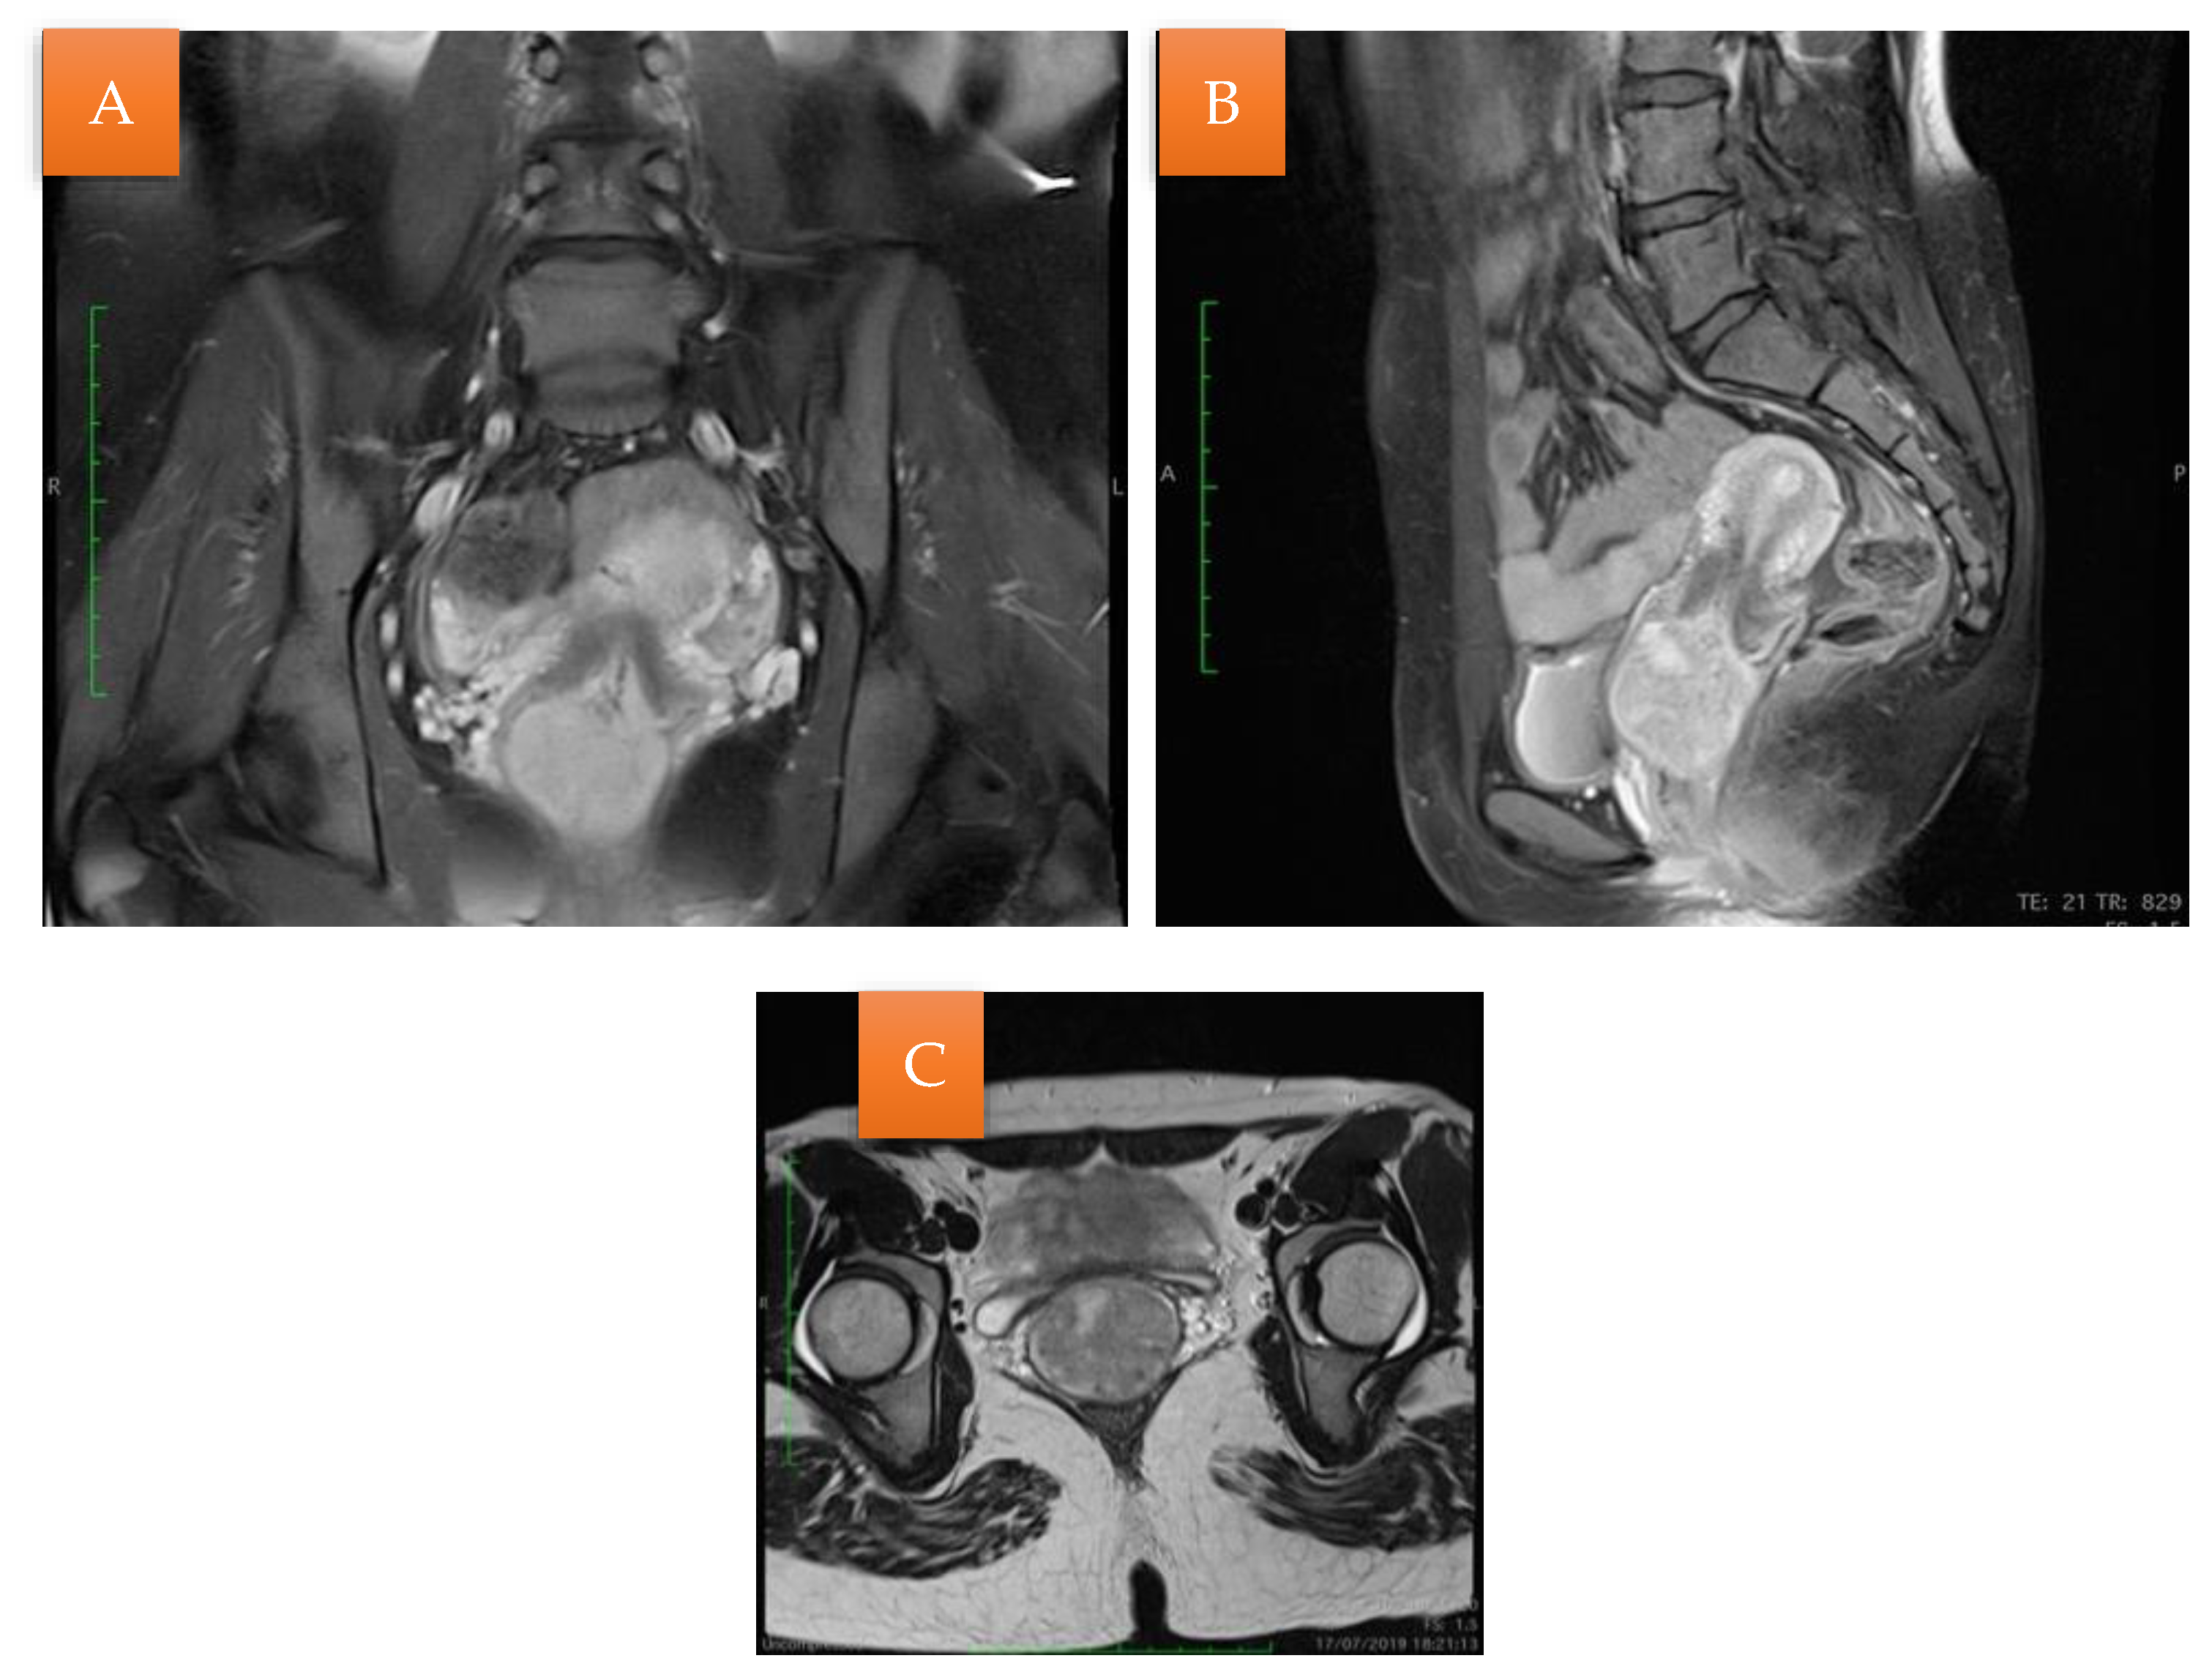

An MRI was performed that described a solid expansive formation, well delimited, with an inhomogeneous structure, with small cystic areas and an intense contrast socket. The mass was located in the vagina, apparently originating from the cervical level, with which it communicates over a distance of 4 mm, presenting the overall dimensions of 44/47/47 mm. The uterine body, the ovaries, and the pelvic organs were within normal limits. No images of pelvic adenopathies were revealed (Figure 2).

Figure 2. MRI examination (A); Sagittal section: the mass originating from the cervical level with small cystic areas (B); Coronal section: the vaginal mass with small cystic areas (C).